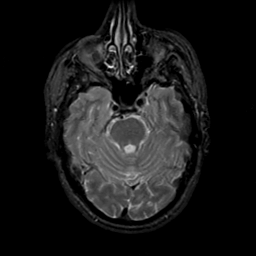

MR Study #19, August 25, 1991 -- Slice #15

[Home][Help][Clinical][Tour 1][Tour 2] Slice 15